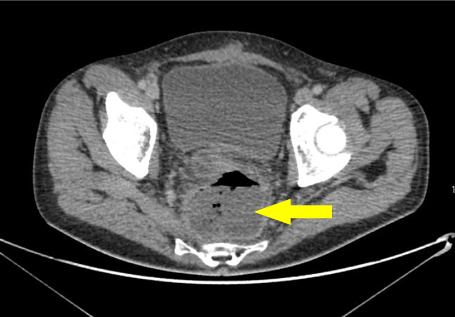

Drainage continued steadily for a further 4 days after which the inflammatory markers had reduced and the rectal funnel was removed. Repeat imaging confirmed successful resolution of the presacral collection (Figure 3). This avoided further need for surgery.

Figure 3: MRI of coronal T2 image of the rectal stent in situ (arrowed). View Figure 3